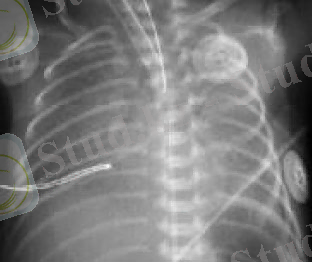

Диагностикасы. Тынысалудың дистресс-синдромын диагностикалауда рентгенологиялық әдіс қолданылады. Рентгенологиялық белгілері патологиялық процесстің дамуына байланысты. Оларды Е. К. Колесников бойынша төртке бөліп қарастырады.

Рентгенографияда - өкпенің екі жағы да диффузды инфильтрат байқалады.